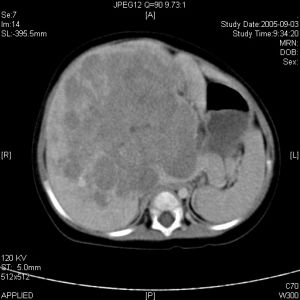

腫瘤細胞與其他疾病基本相似,腫瘤的診斷以病史和身體檢查為最基本、最重要的診斷手段。身體檢查包括X射線檢查、超聲檢查、內窺鏡檢查、組織學活檢、血液檢查等,這裡我們主要講講腫瘤標誌物。